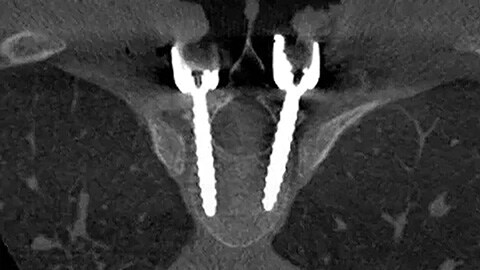

Performing minimally invasive spine procedures in the hybrid OR of University Medical Center Schleswig-Holstein (UKSH), Kiel, Germany As physicians perform more minimally invasive spine surgery procedures, many are working in a Hybrid Operating Room (OR). The Orthopedic and Emergency Surgery team at the University Medical Center Schleswig-Holstein (UKSH) explains the benefits they have experienced over the past three years of performing minimally invasive spine surgery in Philips Hybrid OR.

Performing minimally invasive spine surgery in a Hybrid room with navigation Clinical experience with Philips intra-operative imaging and Brainlab navigation for MIS spine surgery in a Hybrid OR by Dr. Torres, Neurosurgeon at Centro Medico de Asturias, Spain

Spine suite results one pager Key benefits of Azurion with FlexMove for spine surgery